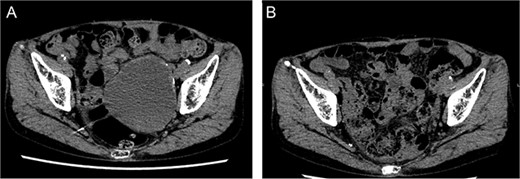

An 80-year-old female was admitted for the expansion of a left CIAA and IIAA. Ten years prior, she had undergone coiling of peripheral branches of the IIAA and stent graft placement in the CIAA. Contrast-enhanced CT showed the IIAA and CIAA extending into the deep pelvis. The maximum short diameter was 90 mm, and there were no signs of endoleak (Fig. 4).

Preoperative computed tomography imaging showing a left common iliac artery aneurysm and internal iliac artery aneurysm with a maximum short diameter of 90 mm. A—Axial image, B—3D image. LCIAA, left common iliac artery aneurysm.

Postoperative computed tomography showing a reduction in aneurysm size. A—Preoperative image, B—7-month postoperative image.